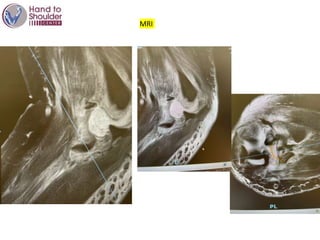

MRI

Still dislocated

CORONOIDE IS THE KEY !

Controlled by MRI